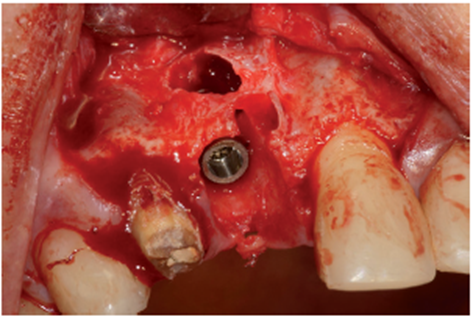

O procedimento cirúrgico foi iniciado através de uma anestesia infiltrativa com articaína 4%. Foram realizadas incisões relaxantes (Figura 4) para expor o leito cirúrgico e, consequentemente, a lesão periapical (Figura 5). Após o deslocamento do retalho, foi realizada a exodontia de forma atraumática (Figura 6) e na sequência, foi feita a curetagem do alvéolo removendo todo o tecido de granulação (Figura 7). Uma vez realizada a toalete do leito cirúrgico (Figuras 8 e 9), o implante Cone Morse Due Cone de 3.5 X 13 mm (Implacil De Bortoli) foi instalado seguindo o melhor posicionamento dentro do rebordo residual, conforme planejado (Figuras 10 e 11). Em sequência, foi realizada a instalação do Cover Screw (Figura 12) e o preenchimento do defeito ósseo com biomaterial (Bio-Oss 0,25), conforme figuras 13 e 14). O fechamento foi realizado com membrana de PTFE-d (Cytoplast TXT–200, Osteogenics – Lubbock TX, EUA), customizada para ser adaptada sobre o defeito ósseo, estendendo-se de 3 a 5 mm da margem do defeito ósseo e intencionalmente exposta (Figura 15). A sutura foi realizada com fio de PTFE (Cytoplast), como podemos observar na figura 16, e instalado um provisório adesivo na região (Figura 17).